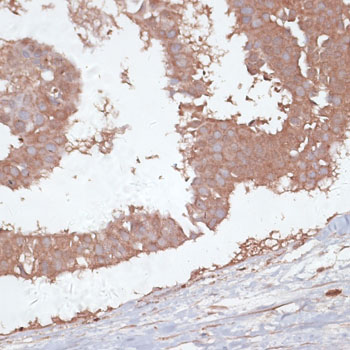

Immunohistochemistry of paraffin-embedded human breast using TGFBR2 at dilution of 1:100 (40x lens).

,

Immunohistochemistry of paraffin-embedded human mammary cancer using TGFBR2 at dilution of 1:100 (40x lens).